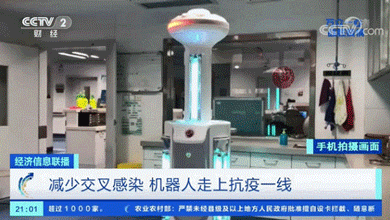

消毒机器人

基本各个医院的消毒工作也是交给机器人,机器人可以在无需人工干预的情况下自己进入隔离区消毒,钛米这款机器人包括了紫外线灯、过氧化氢、次氯酸等多种消毒方式,能够对医院内的流动空气和物体表面进行高水平杀菌。

隔离病人和疑似患者人数持续增加,医护人员面临着体力和精神上的巨大挑战,加速消耗的医疗物资也纷纷告急。

为了尽可能减少个体接触、降低交叉感染的可能性,服务型机器人纷纷“出战”。

服务型机器人可承担起送药、送餐进隔离区以及回收被服和医疗垃圾的工作。

它们分工明确,通过控制中心智能调度即可实现自主开关门、自主搭乘电梯、自主避障、自主充电等功能,无需人员操作,极大地减少了医护人员进入隔离区的频次,起到较好的隔离保护作用。